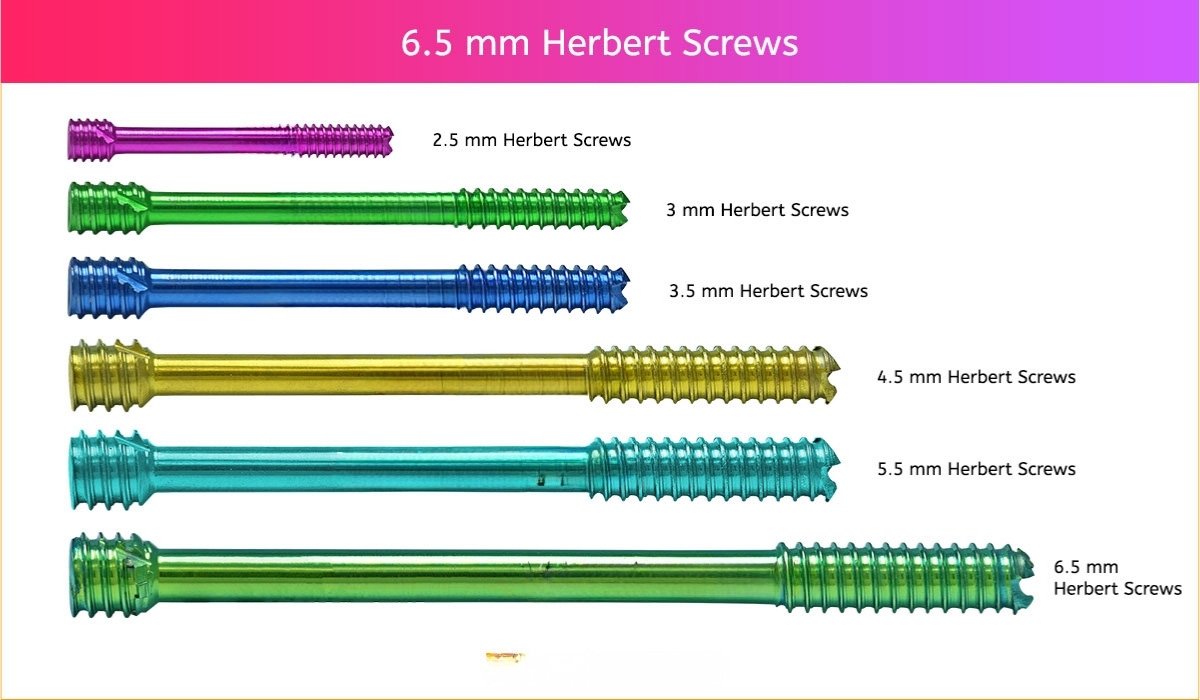

6.5 mm Herbert Screw

6.5 mm Screws Length

12mm, 14mm, 16mm, 18mm, 20mm, 22mm, 24mm, 26mm, 28mm, 30mm, 32mm, 34mm, 36mm, 38mm, 40mm, 42mm, 44mm, 46mm, 48mm, 50mm, 55mm, 60mm, 65mm, 70mm, 75mm, 80mm, 85mm, 90mm, 95mm, 100mm, 105mm, 110mm, 115mm and 120mm.

- 5.5 mm and 6.5 Herbert Screws are indicated for fracture fixation, reconstruction, osteotomy, and arthrodesis of various bones and bone fragments including joint fusions (arthrodeses) in the foot and fixation of intra-articular fractures of the humerus, femur and tibia.